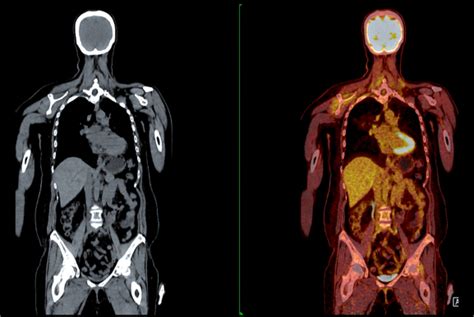

全身热CT靠谱吗:深入解析热成像体检的.